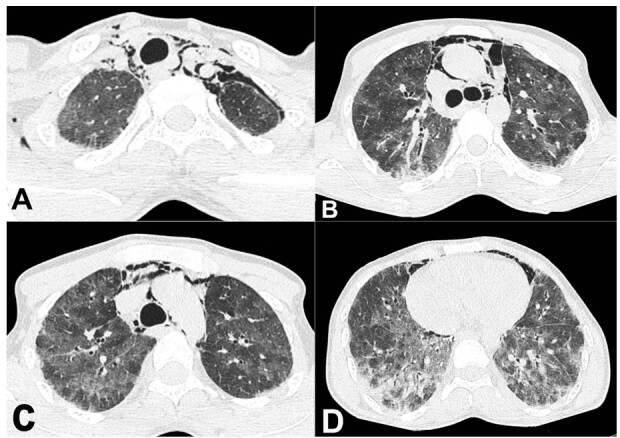

Dermatomyositis is a heterogeneous systemic disease, with 7% to 10% of the individuals presenting the Anti MDA-5 antibody. This subset of patients has clinically amyotropic dermatomyositis, presenting with cutaneous ulcer and rapidly progressive interstitial lung disease. We report the case of a 22-year-old male with a six-month history of low-grade fever associated with myalgia, polyarthralgia, and marked weight loss. He had a history of shortness of breath and high-grade fever 15 days before admission. His clinical features and imaging workup were consistent with acute respiratory distress syndrome. A nasal swab was positive for H1N1 influenza virus infection. During the disease investigation, he succumbed after nine days of admission. The autopsy examination showed diffuse alveolar damage on a background of non-specific interstitial pattern of injury in the lungs. His postmortem muscle biopsy revealed subtle changes of inflammatory myopathy. The brain showed diffuse subarachnoid hemorrhage. Evaluation of postmortem serum sample revealed positivity for Anti MDA-5 and Ro-52 antibodies. This was a case of Anti MDA-5 and Ro-52 associated dermatomyositis with non-specific interstitial pneumonia pattern of lung injury complicated with H1N1 influenza pneumonia, leading to diffuse alveolar damage and subsequent respiratory failure and death. Serum Anti MDA-5 antibodies represent an important biomarker for diagnosing and predicting prognosis for patients with idiopathic inflammatory myopathies, especially clinically amyopathic dermatomyositis. Anti-Ro-52 has been reported in a wide variety of autoimmune diseases, particularly in myositis, scleroderma, and autoimmune liver diseases. Ro-52 autoantibodies are associated with interstitial lung disease (ILD), and their presence should encourage the clinician's curiosity to search for ILD.